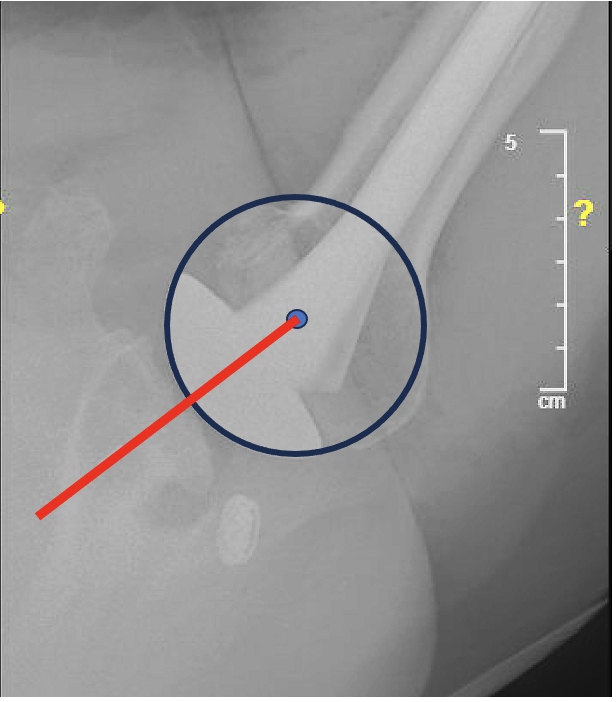

The preoperative axillary view shows the humeral head to be posteriorly decentered on the retroverted glenoid.